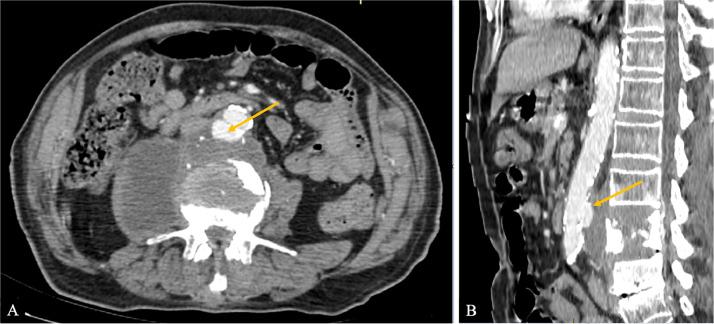

Mycotic aneurysms are a rare but potentially life-threatening complication of infections, particularly those involving the spine. Spondylodiscitis, a bacterial or fungal infection of the intervertebral disc, is a known risk factor for the development of mycotic aneurysms. Early diagnosis and prompt treatment are crucial for improving patient outcomes. We report the case of a 79-year-old patient with a history of diabetes admitted for chronic back pain refractory to medical treatment. A cervico-thoraco-abdomino-pelvic CT scan showed infectious spondylodiscitis at the lumbar level complicated by a mycotic aneurysm of the infrarenal abdominal aorta. This case highlights the diagnostic challenges associated with mycotic aneurysms, particularly when they arise from a contiguous infectious focus. Imaging modalities, such as computed tomography (CT) and magnetic resonance imaging (MRI), play a pivotal role in identifying these aneurysms and assessing their extent. The patient underwent surgical management of the spondylodiscitis and the mycotic aneurysm. A stent was placed to reinforce the weakened aortic wall and prevent rupture. Postoperative management included long-term antibiotic therapy to eradicate the infection. The patient experienced a favorable outcome, with resolution of symptoms and improved quality of life.

真菌性动脉瘤是感染的一种罕见但可能危及生命的并发症,尤其是涉及脊柱的感染。脊椎椎间盘炎,即椎间盘的细菌或真菌感染,是真菌性动脉瘤发生发展的已知危险因素。早期诊断和及时治疗对于改善患者预后至关重要。我们报告一例79岁有糖尿病史的患者,因药物治疗无效的慢性背痛入院。颈胸腹部盆腔CT扫描显示腰椎水平存在感染性脊椎椎间盘炎,并伴有肾下腹主动脉真菌性动脉瘤。该病例突出了与真菌性动脉瘤相关的诊断挑战,尤其是当它们源于相邻感染灶时。诸如计算机断层扫描(CT)和磁共振成像(MRI)等成像方式在识别这些动脉瘤及其范围评估中起着关键作用。患者接受了脊椎椎间盘炎和真菌性动脉瘤的手术治疗。放置了一个支架以加固薄弱的主动脉壁并防止破裂。术后管理包括长期抗生素治疗以根除感染。患者预后良好,症状缓解,生活质量改善。